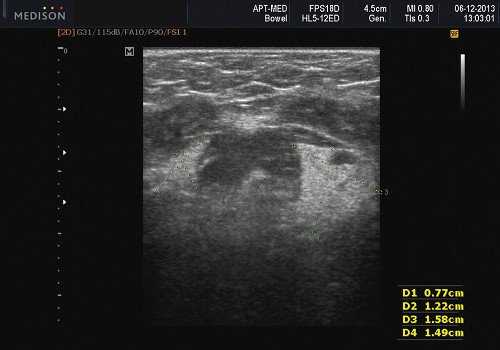

Теория и практический опыт в ультразвуковой диагностике патологии слюнных желез

В отечественной и зарубежной литературе встречается много работ, посвященных сиалогии (от греч. Sialon - слюна и logos - учение) - науке о заболеваниях и повреждениях слюнных желез, методах их диагностики и лечения. По данным разных авторов, на долю заболеваний слюнных желез приходится до 24% всей стоматологической патологии. В настоящее время в клинической практике наиболее часто встречаются дистрофические, воспалительные заболевания слюнных желез (сиалоаденозы, сиалоадениты), а также опухоли и врожденные пороки развития слюнных желез. Кроме того, патологические изменения слюнных желез часто сопутствуют другим заболеваниям (сахарный диабет, бронхоэктатическая болезнь, саркоидоз, цирроз печени, гипертриглицеридемия, лимфогранулематоз и др.).

- ультразвуковой метод (является наиболее доступным, безопасным и информативным в процессе дифференциальной диагностики патологического состояния слюнных желез).

Патология слюнных желез

- обструктивные сиаладениты, развивающиеся при затруднении оттока слюны при обструкции выводного протока камнем (рис. 5-7) или сгустившимся секретом, а также вследствие рубцового стеноза протока. По распространенности процесса различают очаговый, диффузный сиаладениты и сиалодохит - воспаление выводного протока. Течение процесса может быть острым и хроническим;

Рис. 5. Камень протока поднижнечелюстной слюнной железы.

Рис. 6. Камень в паренхиме поднижнечелюстной слюнной железы.

Рис. 7. Камень в протоке поднижнечелюстной слюнной железы.